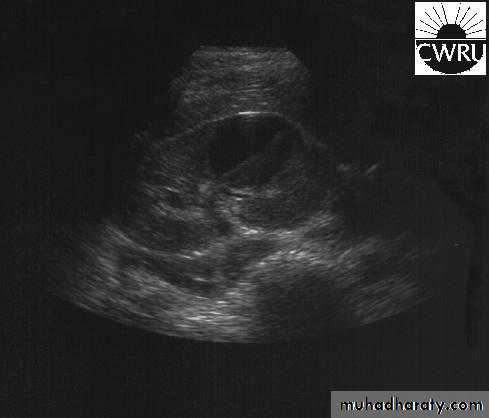

U/S: cystic cortical lesion with internal echoes.

U/S cystic lesion with internal echoes (renal abscess)

Left renal abscessCT scan: right renal abscess

CT scan: Left renal abscess